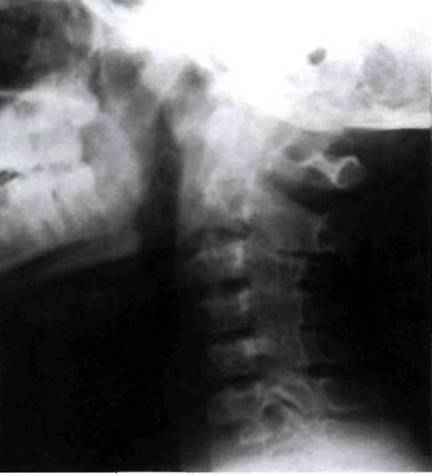

Рис. 23-14. Анкилоз дугоотростчатых сочленений в шейном отделе позвоночника у больного ЮАС.